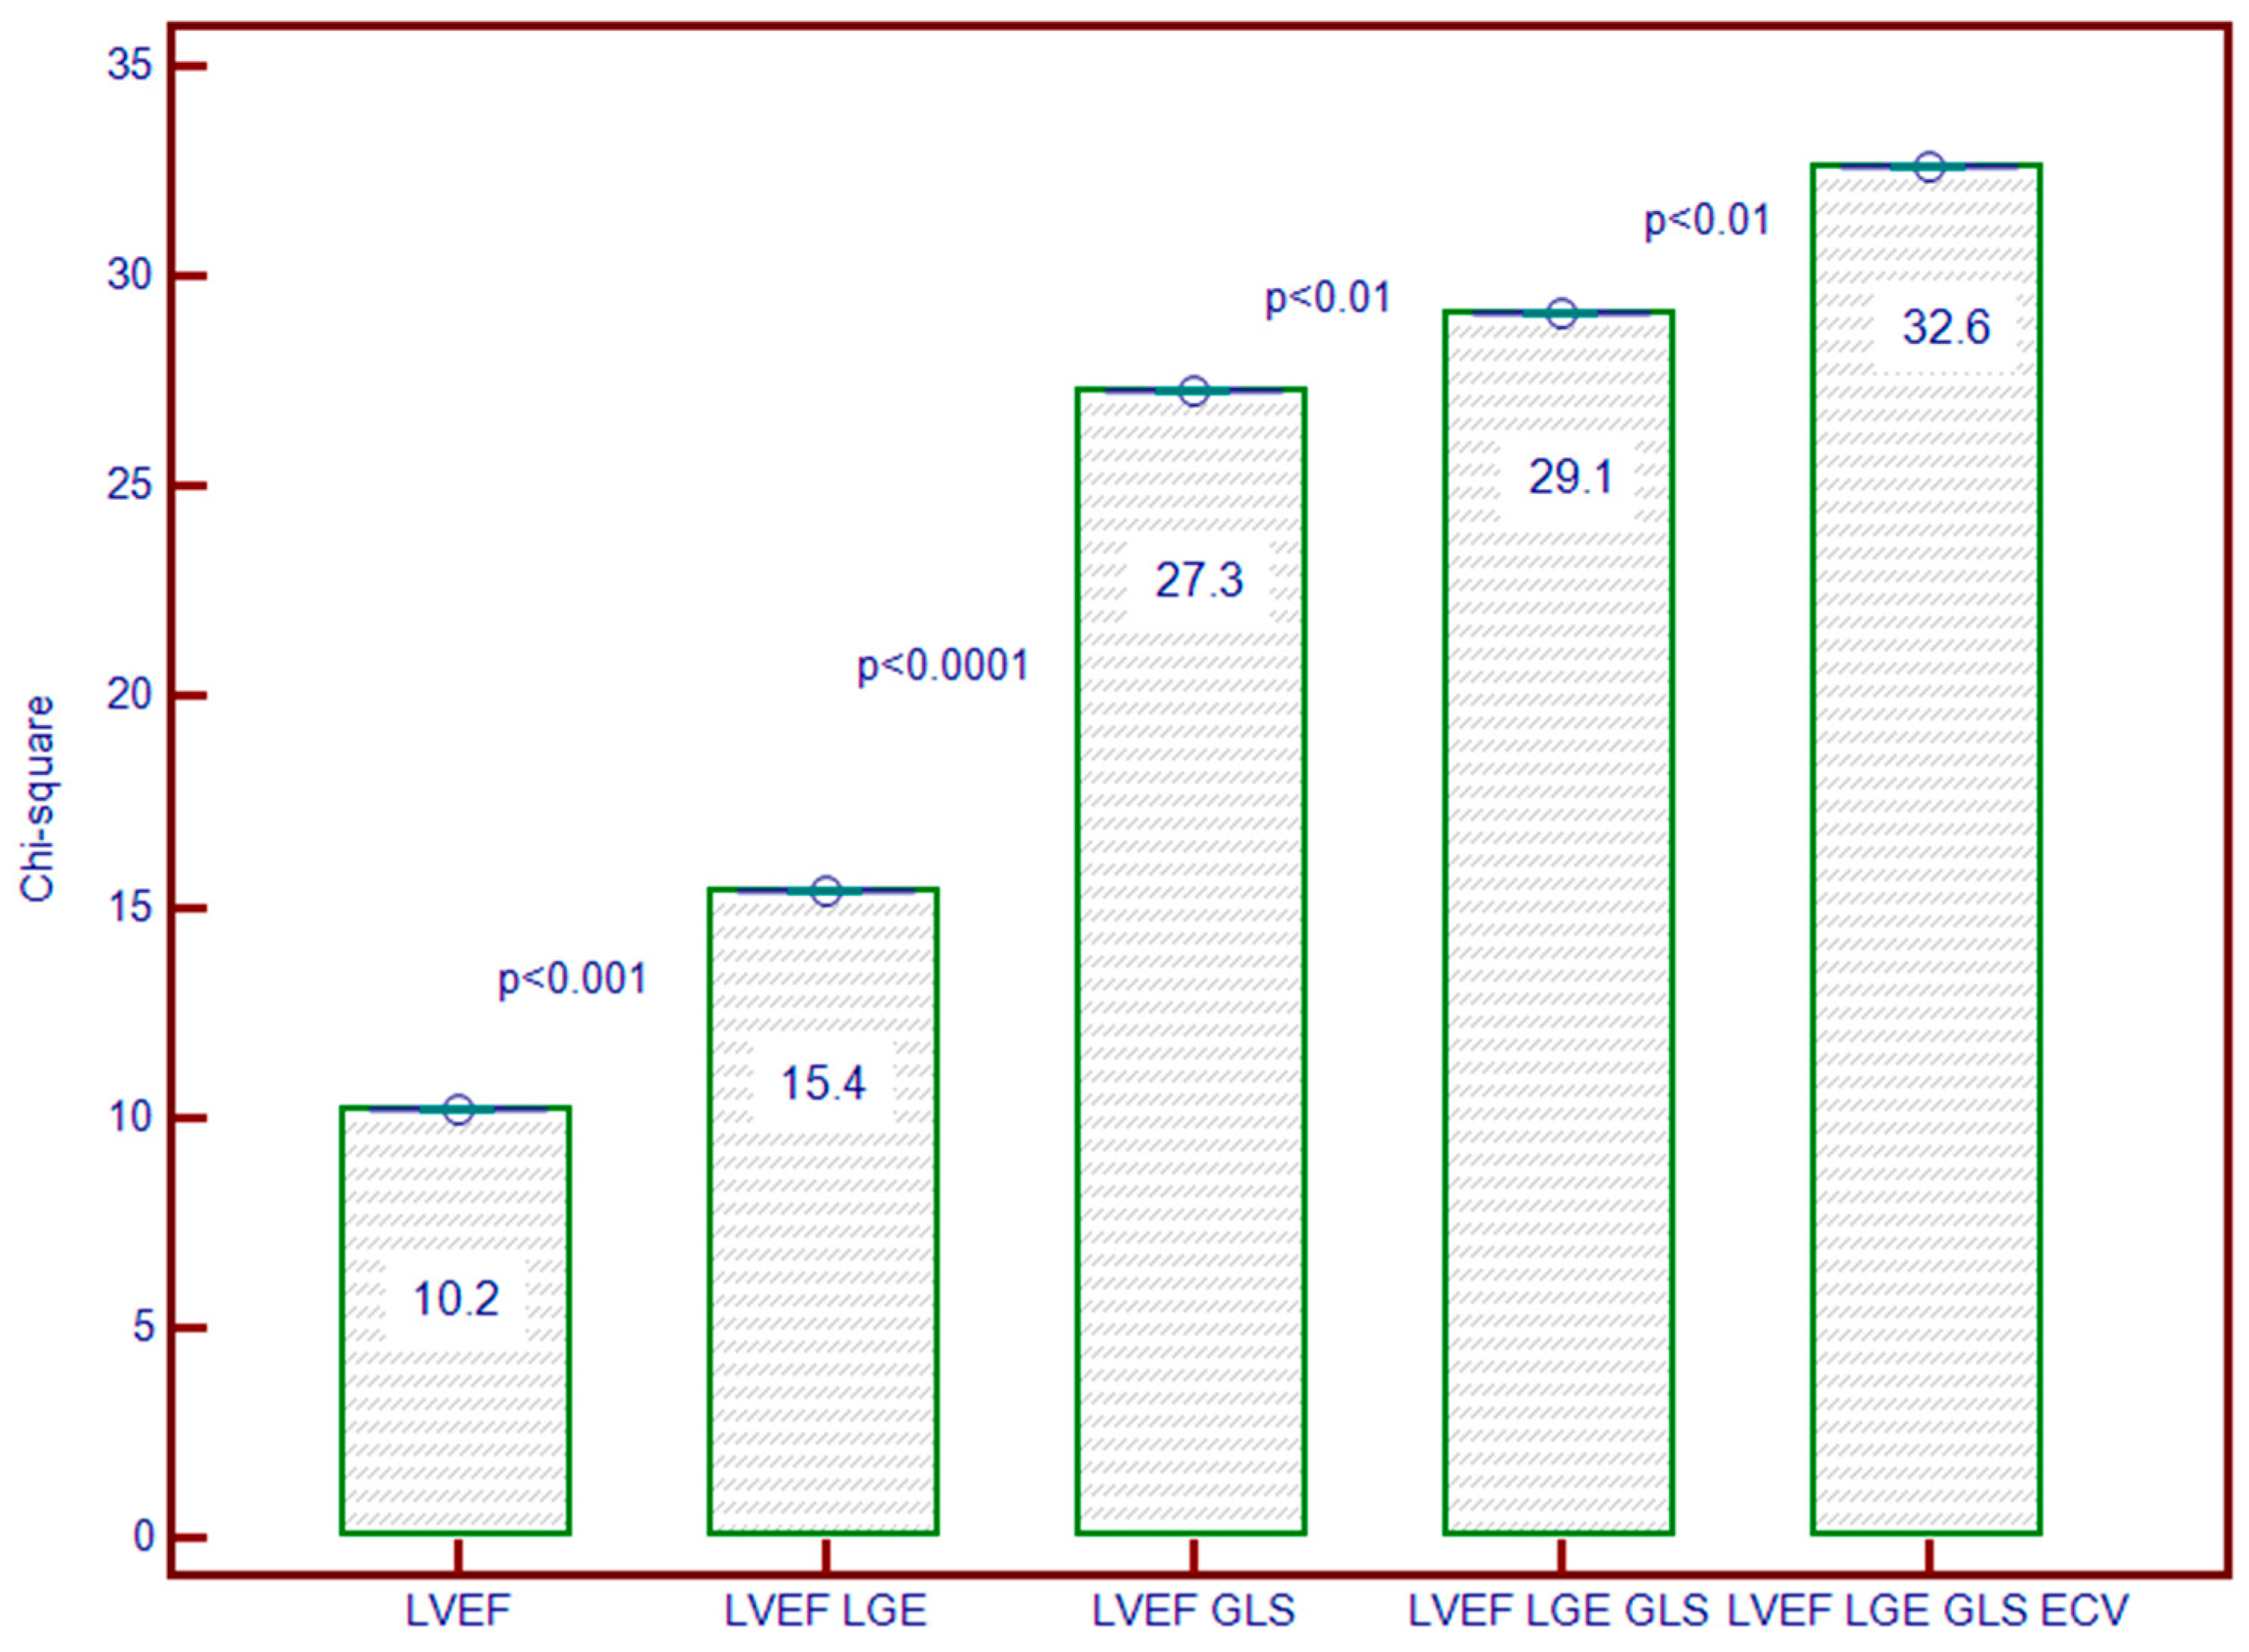

3.7. Incremental Predictive Ability of LV Strain for Predicting MACEs